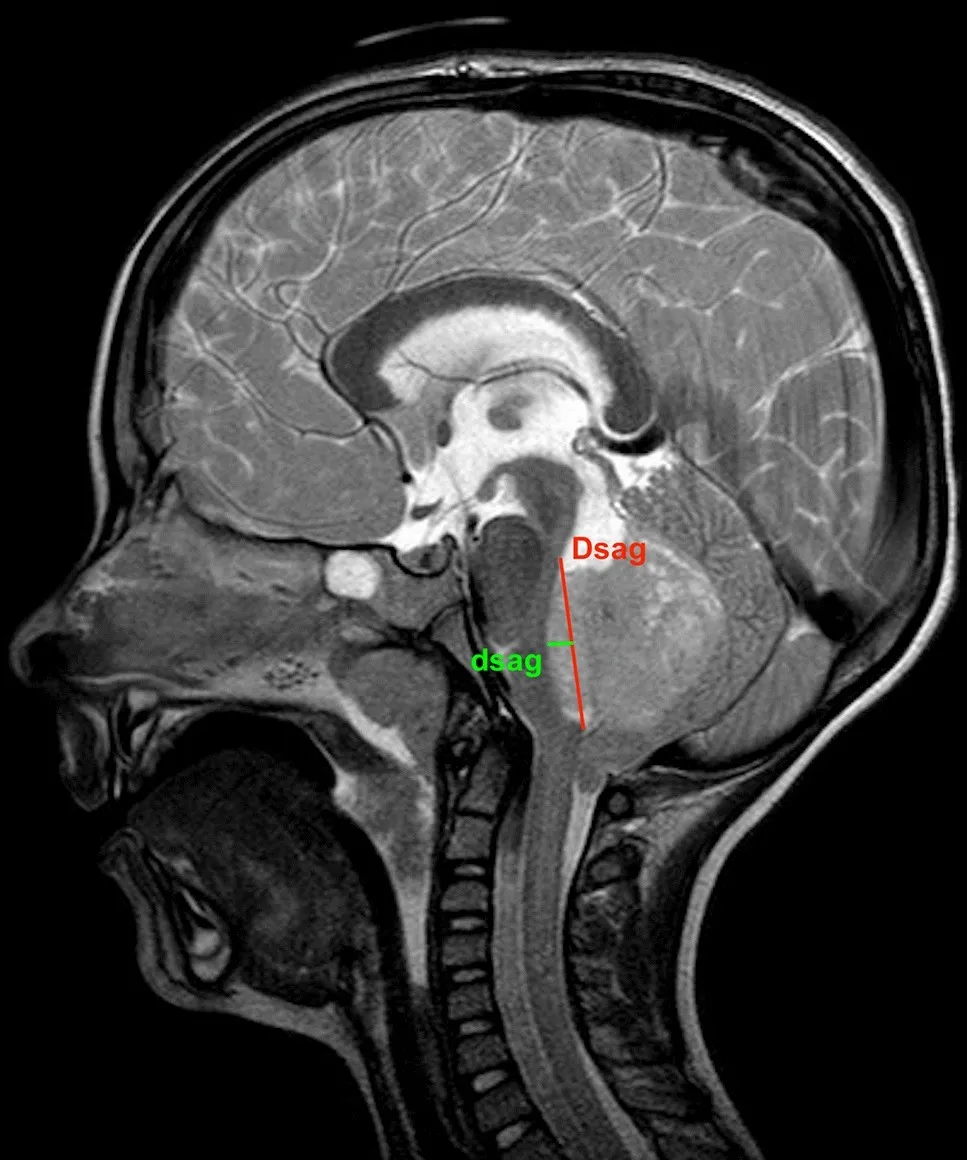

Magnetic Resonance Imaging (MRI) is the imaging modality of choice for evaluating posterior fossa tumors. MRI provides superior soft tissue contrast and helps identify tumor type, location, and extent. Diffusion-weighted imaging (DWI) and apparent diffusion coefficient (ADC) measurements offer additional insights into tumor cellularity and malignancy potential. Advanced MRI sequences help differentiate between tumor types such as medulloblastomas (which show restricted diffusion due to high cellularity) and pilocytic astrocytomas (which typically lack diffusion restriction).

Imaging: Advanced MRI including DWI, conventional sequences, and spinal imaging when indicated to characterize tumor and assess for metastatic disease.